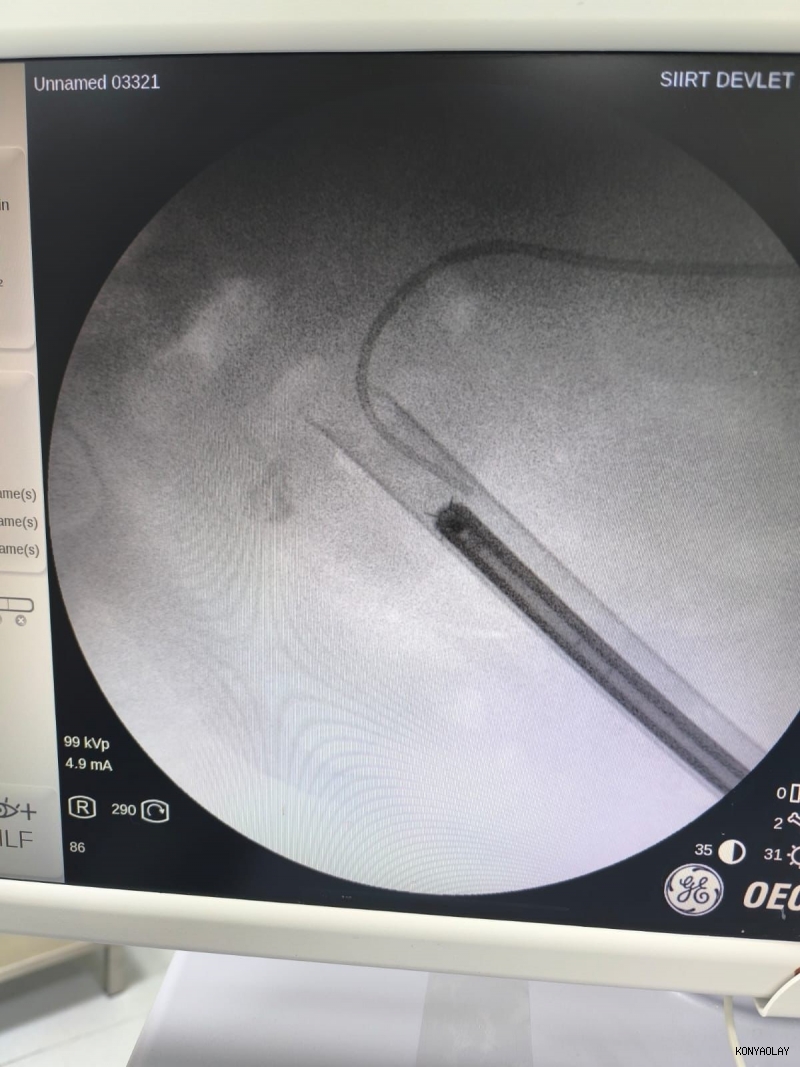

Siirt'te 34 yaşındaki Fatih Aslan, ateş, üşüme ve idrar yaparken yanma şikayetleriyle hastaneye başvurdu. Yapılan muayene ve testlerin ardından piyelonefrit (böbrek iltihabı) tanısı konuldu ve enfeksiyon tedavisi tamamlandı. Üroloji uzmanı doktor Miraç Ataman, gerçekleştirilen operasyon, hem tıbbi açıdan hem de toplumsal sağlık açısından önemli bir başarı olduğunu söyledi. Ataman, "34 yaşındaki erkek hastamız, ateş, üşüme ve idrar yaparken yanma şikayetleri ile acil servise başvurdu. Yapılan değerlendirme sonucunda piyelonefrit (böbrek iltihabı) tanısı konuldu ve yatış yapılarak enfeksiyon tedavisi başarıyla tamamlandı. Tanı sürecinde yapılan Bilgisayarlı Tomografi (BT) görüntülemesinde böbreğin tamamını kaplayan, sert yapıda(950-1450 HU), literatürde staghorn olarak adlandırılan ve halk arasında ‘ geyik boynuzu taşı ’ diye bilinen büyük taş saptandı. Staghorn taşlar böbreğin tüm boşluklarını doldurup, tekrarlayan enfeksiyonlara ve uzun vadede böbrek fonksiyon kaybına yol açabildiğinden tedavisi hayati önem taşımaktadır. Biz de bu vakamızda, Perkütan Nefrolitotomi (PCNL) yöntemiyle böbreğe küçük bir cilt kesisi üzerinden girerek endoskopik cihazlarla taşları parçalayıp çıkardık. PCNL, özellikle çapı 2 cm’den büyük ve kompleks taşlarda altın standart kabul edilmektedir. Normalde staghorn taşların temizlenmesi uzun süren ve çoğu zaman birden fazla seans gerektiren zorlu bir süreçtir. Modern altyapısı sayesinde, ciltten tek giriş yolu açılarak yaklaşık 1,5 saatlik bir seansta böbreğin tüm taş yükü başarıyla temizlendi" dedi.